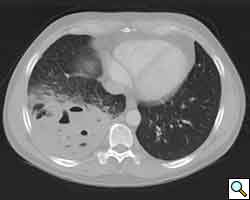

A previously healthy 43-year-old male presented with cough, fevers, and leukocytosis. A chest radiograph (Figure 1) revealed extensive consolidation in the right lower lung containing multiple cavities with air-fluid levels consistent with a necrotizing infection. A chest computed tomogram (Figure 2) showed an abscess cavity and consolidation in the right lower lobe with an aberrant blood supply from the descending aorta. This systemic blood supply was confirmed by subsequent 3D reconstruction (Figure 3). He was initially treated with IV antibiotics, resulting in normalization of his temperature and white blood cell count. He was then discharged home on a 3-week course of oral antibiotics. Three days prior to a planned surgical resection, he underwent angiographic localization of the feeding artery (Figure 4) and coil embolization (Figure 5).